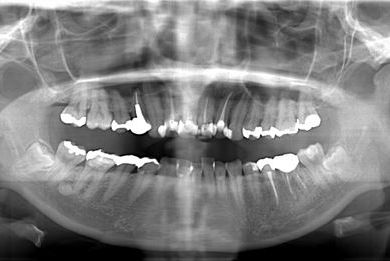

性別/年齢 女性 / 27歳

主訴 他の歯科医院に4ヶ月通院していたが、違和感が治らない。

治療内容 オールセラミック4本(セラミック用の土台4本)

2 1 1 2

総治療費 573,300円

治療期間 9ヶ月

治療前